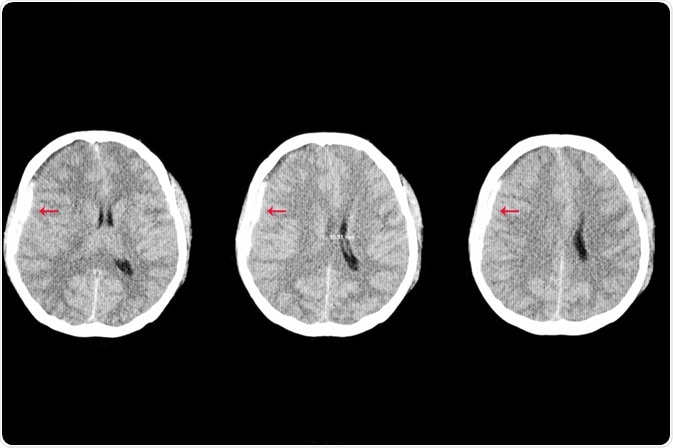

Traumatic Brain Injury

Image Credit: Tomatheart/Shutterstock.com

Certain diagnostic methods, like MRI brain scans, can provide your doctor with the best possible information about the severity of your TBI and determine essential prognostic information. This can help ensure you get the treatment you need.